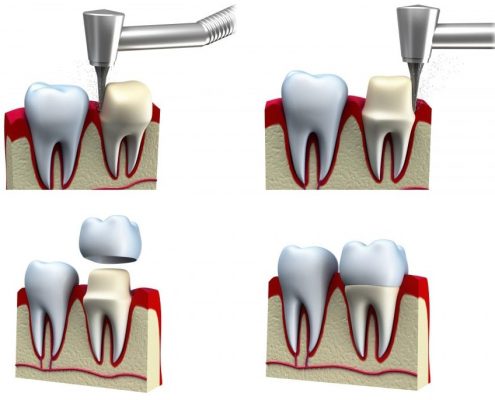

درد دندان روکش شده

دندان روکش شده به دلایل مختلفی می تواند دچار دردهای تیز و آزار دهنده شود.چگونه می توان درد دندان روکش شده را بهبود داد یا درمان کرد؟ درد دندان روکش شده